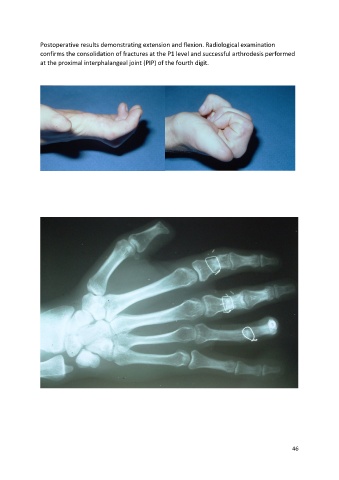

Postoperative results demonstrating extension and flexion. Radiological examination

confirms the consolidation of fractures at the P1 level and successful arthrodesis performed

at the proximal interphalangeal joint (PIP) of the fourth digit.